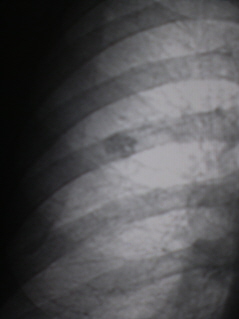

Цифровое стандартное флюорографическое профилактическое исследование (проведено на цифровом флюорографе «РЕНЕКС-ФЛЮОРО»). Справа в 3 межреберье, проекционно на уровне заднего фрагмента 6 ребра, определяется крупноочаговая тень неправильной формы размерами 1,2 х 1,8 см., с нечеткими, неровными контурами, средней интенсивности, неоднородной структуры, с мелкими просветлениями и точечными известковыми включениями (2 – фрагмент флюорограммы с увеличением).

Иллюстрация 2 – увеличенная тень гамартомы.